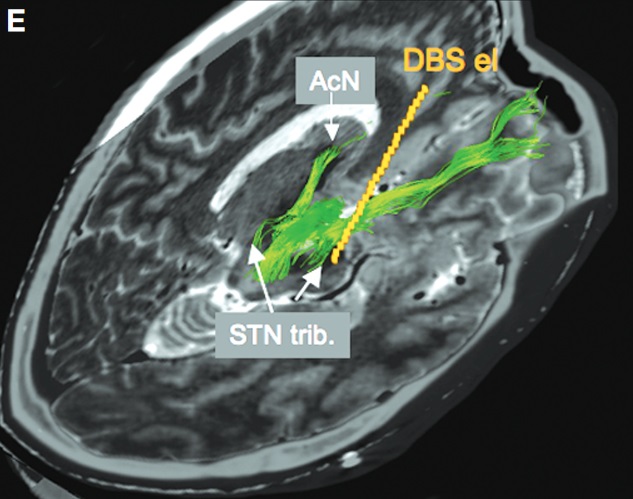

The research group investigated why electrical stimulation of the subthalamic nucleus sometimes causes patients to develop hypomania. (Coenen et al. 2009)

When they visualized the nerve fibers in the patients' brains, they found that in a patient who developed hypomania, the electrode contact was in direct contact with the medial forebrain bundle.

On the other hand, patients who did not develop hypomania had electrode contacts located further away from the medial forebrain bundle.

The medial forebrain bundle that the electrode was in contact with was not the mainstream originating from the well-known ventral tegmental area, but rather tributaries originating from the subthalamic nucleus.

When the electrode contact of the patient who had developed hypomania was changed one step up so that it did not contact the medial forebrain bundle, the hypomania resolved and the motor symptoms further improved.